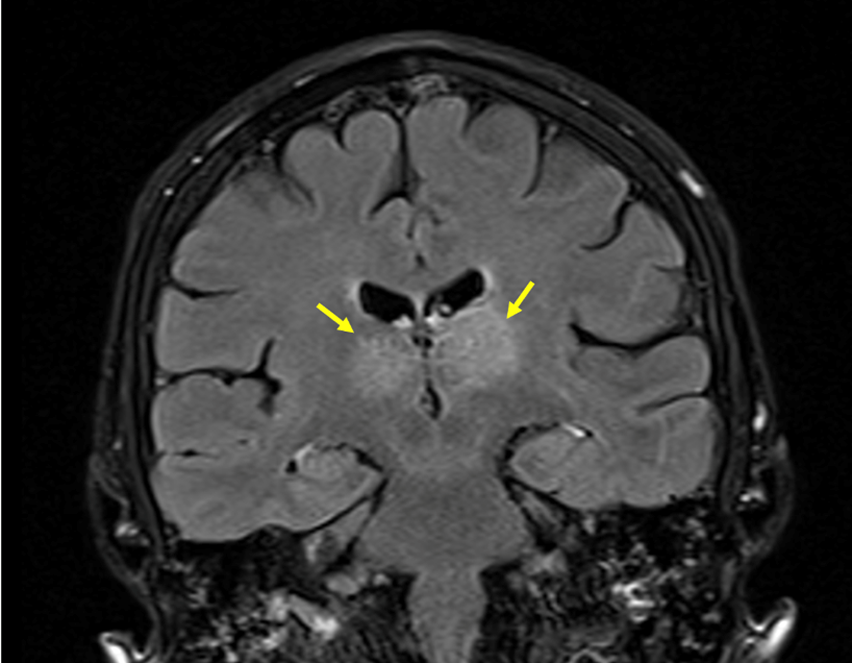

A brain MRI study displayed an extensive CVST, with main involvement of the right transverse and sigmoid sinuses (Figure 1), and extension to the straight sinus and vein of Galen. There were infarction signs in the thalamus (Figure 2) and in the right occipital region, with associated bleeding in this zone (Figure 3).

Fig. 2  MRI FLAIR sequence showing bilateral thalamic hyperintensity related to parenchymal infarcts (yellow arrows, coronal view).